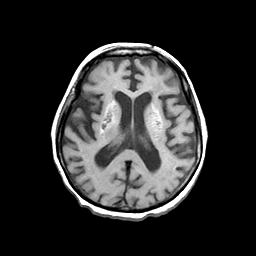

Basal Ganglia Calcification: T1-weighted MR -- Slice #10

[Home][Help][Clinical] Slice 10